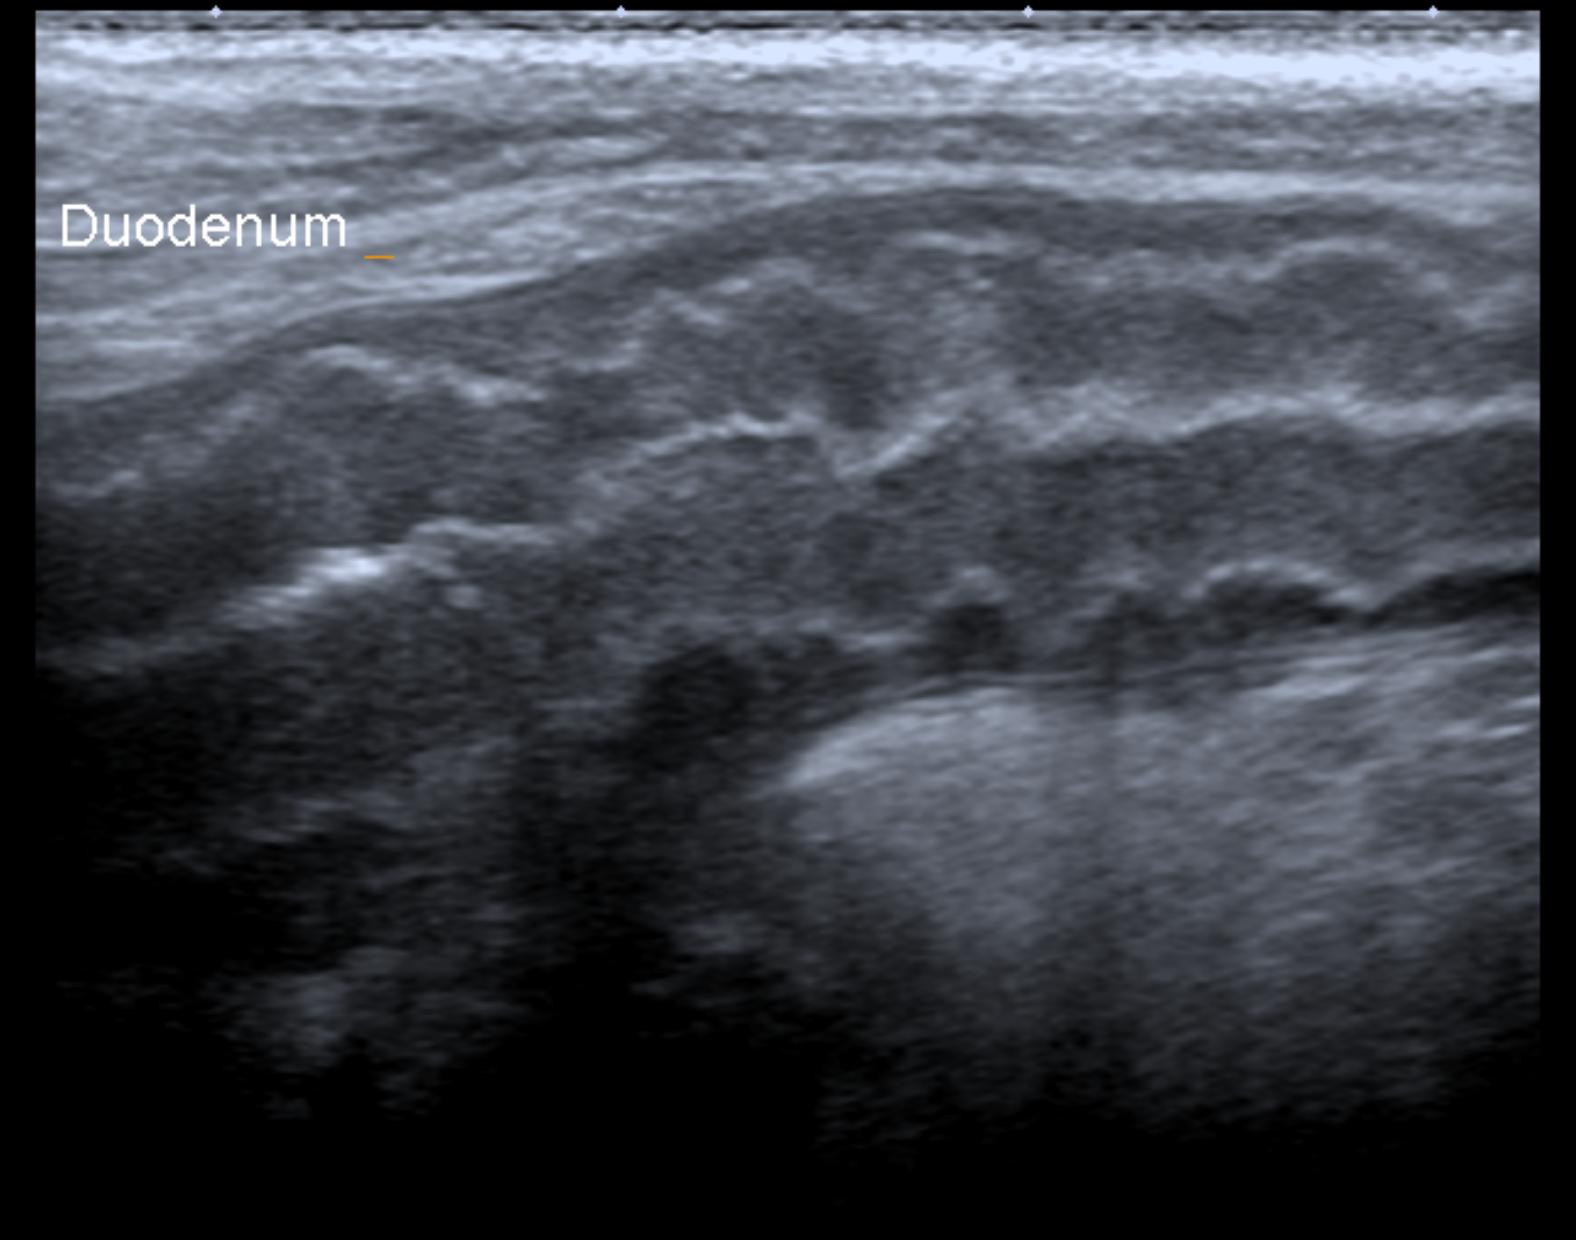

血液検査では膵臓から分泌されるLIP (リパーゼ)値上 昇、炎症があるときに上がるCRPの上昇が見られることが多いです。また、外部への依頼検査で、確定 診断として犬特異的膵リパーゼ(c-PLI)を測定する こともあります。 超音波検査では膵臓の腫大・膵臓周囲の高エコー源 生・十二指腸まで炎症が波及することによる十二指腸のコルゲートサイン(うねうねしてみえる)が指 標となります。

十二指腸のコルゲートサインです。

膵臓が炎症により高エコーとなりモヤモヤして見えるのが分かります。